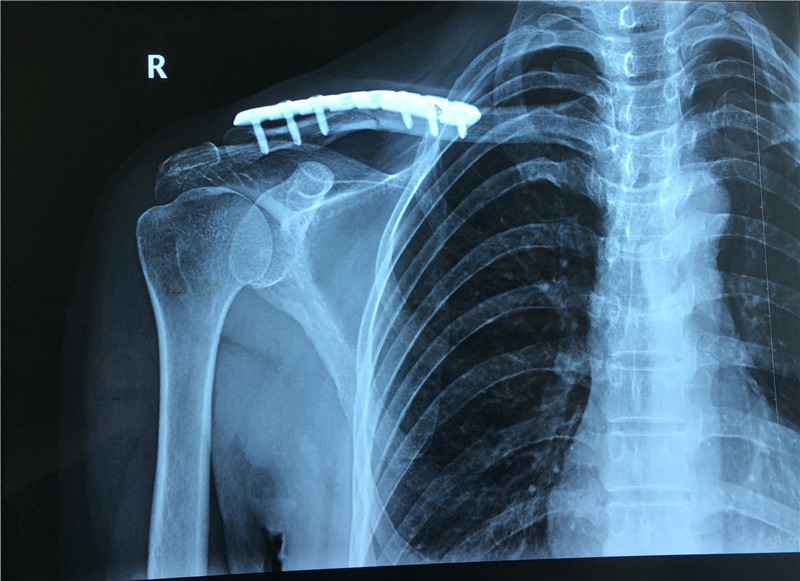

骨性关节炎,虽然传统的治疗方法玻璃酸钠、封闭等手段可以发挥效果,有效地减轻天气变化时的关节不适,但是传统治疗方法存在一定的局限性和副作用,治疗不当将对预后产生不良影响。随着富血小板血浆(PRP)技术的产生,传统治疗方法被逐渐替代,甚至淘汰,PRP技术开始广泛应用于骨科、运动医学等多个学科,尤其是骨科,在骨与关节、肌腱疾病方面的治疗。 46岁的女性患者曾某,九个月前不慎发生交通事故,诊断:右侧锁骨骨折,并行“锁骨骨折切开复位内固定术”。患者既往有严重家族遗传性贫血,术后九月骨折未愈合,来我院就诊,要求干预治疗,考虑可行植骨术或PRP等治疗,患者选择创伤小、几乎无副作用的PRP技术。在骨科吴富华主任医师带领下的PRP治疗团队,成昌桂、付明辉、陆海涛、郭长征等医师于上周成功施行PRP治疗,留观一天后出院,完成我院首例PRP技术。 术前X片: